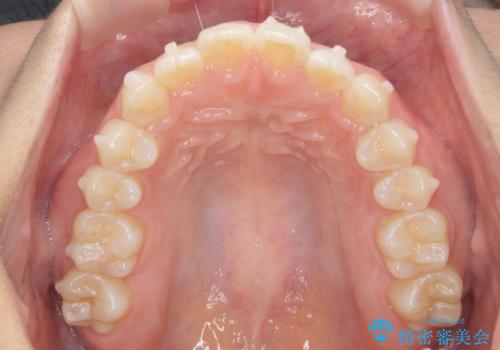

前歯のすれ違い インビザラインで行うマウスピース矯正

- 前歯のガタつき、でこぼこ、前後が逆になっている噛み合わせの改善を求めて来院されました。

治療の装置が目立たず歯ブラシのしやすいマウスピース矯正インビザラインでの治療を計画します。

20時間/日の装用時間をしっかりと守っていただき、きれいな歯並びを手に入れることができました。